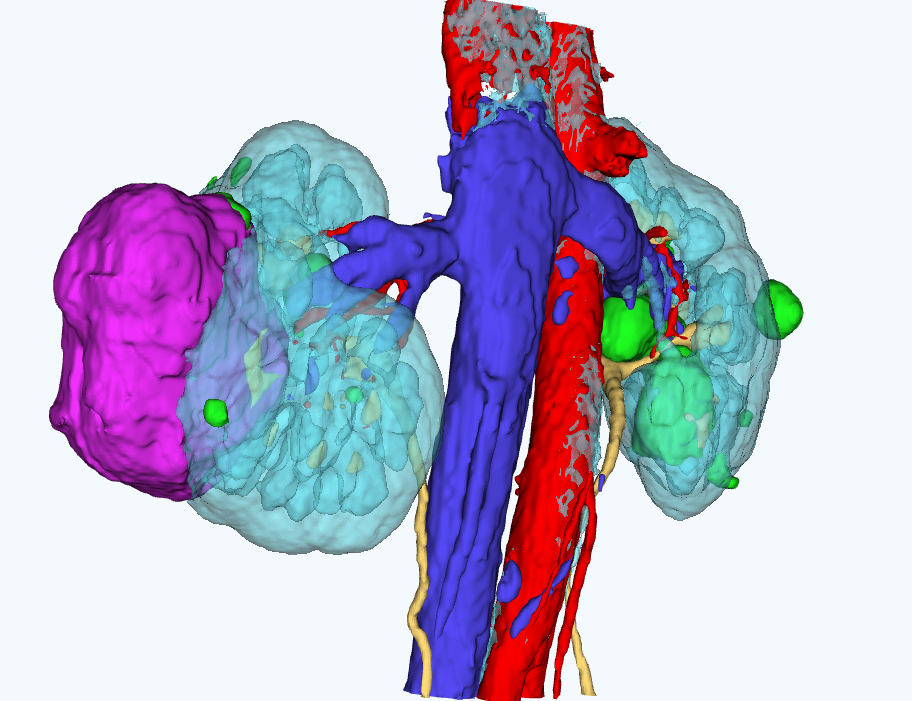

для планирования оперативного вмешательстваСервис создает интерактивные виртуальные 3D модели пациента на основе снимков компьютерной томографии

Персонализированная анатомия

Сервис позволяет выделить расположение артерий, вен, мочеточников, новообразований и паренхимы почки пациента.

Работа с 3D моделью

Врач может работать с 3D моделью для изучения анатомических особенностей пациента